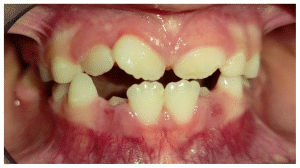

The patient was a young female presenting with a Class III dento-skeletal malocclusion, which was treated using the AMCOP® TC appliance. A comprehensive diagnostic protocol was carried out both before and after treatment, including orthopantomography (Figure 2–3), postero-anterior teleradiography (Figures 4, 5), latero-lateral cephalometric radiography (Figures 6, 7), cephalometric analysis (Tables 1, 2), as well as extraoral (Figures 8, 9) and intraoral photographs (Figures 10, 11). The extraoral examination revealed an edge-to-edge incisal relationship and the presence of a midline diastema. Pre-treatment cephalometric analysis (Deltadent® Lana, Bolzano, Italy) confirmed the diagnosis of a skeletal Class III malocclusion. The treatment plan involved the use of the AMCOP® TC appliance. The patient was instructed to wear the device for two hours in the afternoon and throughout the night for the first six months, followed by nighttime use only for an additional six months. Upon completion of the treatment, the patient achieved a Class I occlusion, with correction of both overjet and overbite. Additionally, the device facilitated tongue re-education and contributed to the postural realignment of the first cervical vertebra.